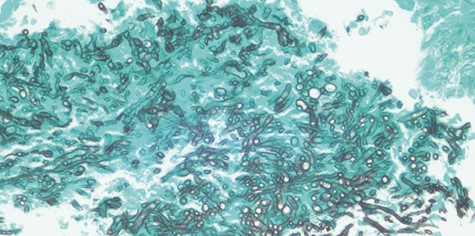

Histopathological examination showed Candida species without evidence of mucosal invasion (Figs. 5 and 6) Intravenous ceftriaxone was commenced for a total duration of 14 days. His symptoms showed significant improvement 1 week after the operation with complete resolution of the headache. His left extraocular muscle functions were slowly restored at 4 weeks post-operation (Fig. 7).

Histopathological examination revealed fungal body (*). No evidence of mucosa invasion was observed.

Gomori’s methenamine silver (GMS) stain of Candida species evidenced by its septate hyphae with characteristic dichotomous branching at an angle of approximately 450.